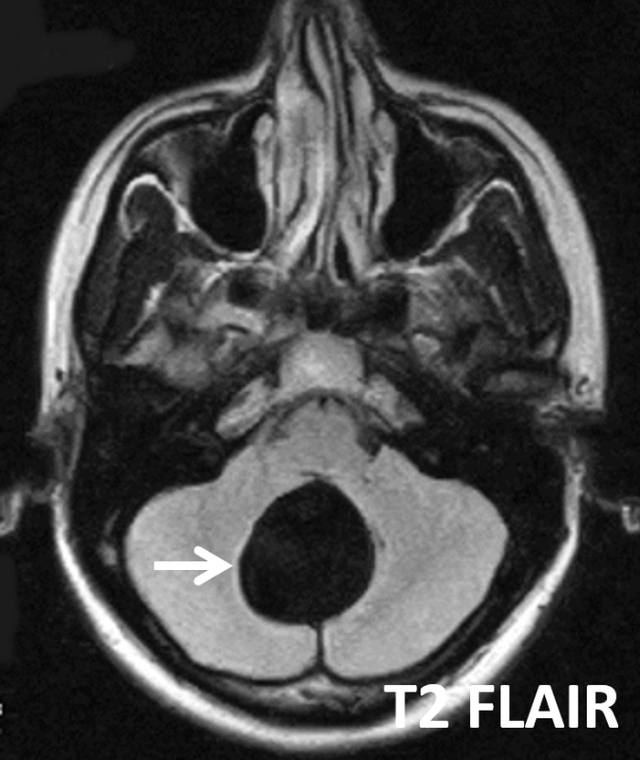

患者女性,29岁,头痛、视物模糊和共济失调。

答案:A. Blake囊肿

Blake囊肿是一种后颅窝的小蛛网膜囊肿畸形,被认为是继发于第四脑室正中孔形成障碍的Blake小袋退化失败所致髓帆向小脑延髓池的囊性扩张。

Blake囊肿经典的影像学表现有后颅窝小脑蚓部(图中黄色箭头)后下方可见一装满脑脊液的囊肿(图中白色箭头),该囊肿后方与小脑延髓池(图中红色箭头)分离。该病例中未见小脑蚓部发育异常,而Dandy-Walker综合征这常伴小脑蚓部发育不全。